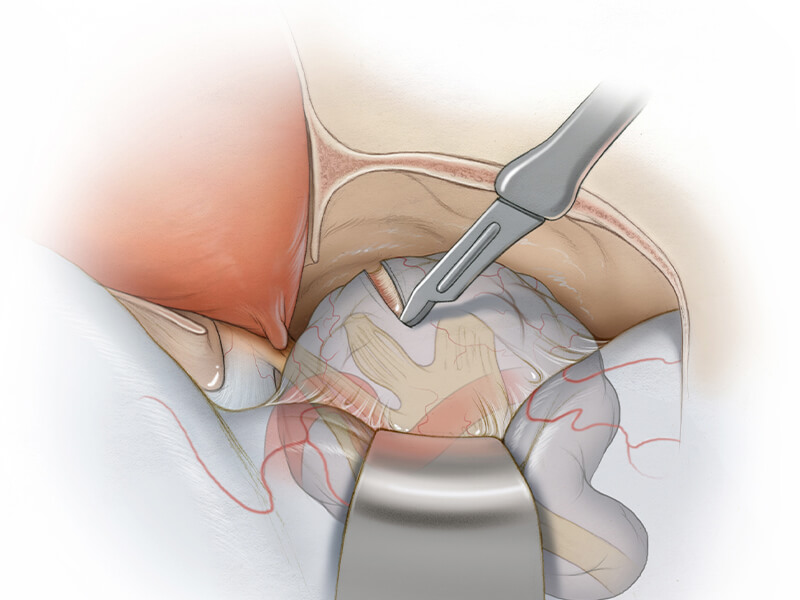

قیمت: 45٬000 تومان - دسته بندی فایل: علوم پزشکیپاورپوینت آشنایی با آپوپلکسی هیپوفیز

خرید پاورپوینت حرفه ای با موضوع آشنایی با آپوپلکسی هیپوفیز از لوکس فایل